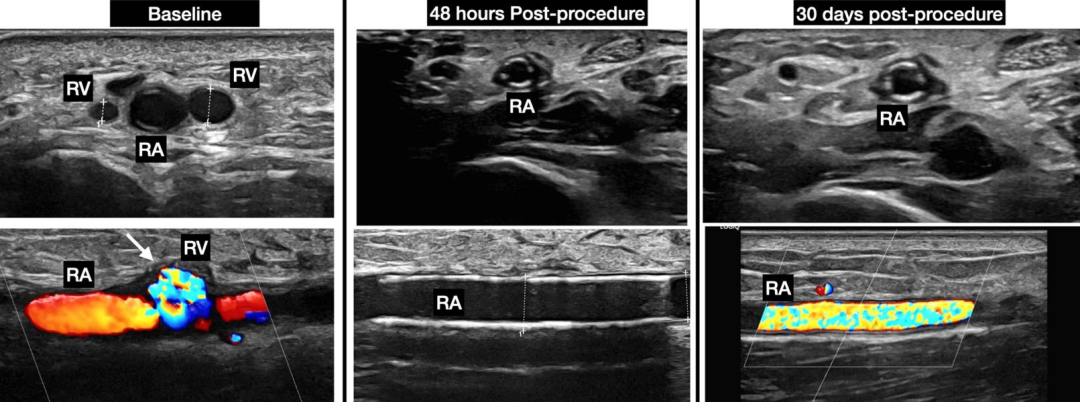

48小时后,再次超声证实AVF已闭合,其中一条伴行的桡静脉出现血栓性闭塞(图7)。

图7.术后48小时超声图像

(A)扩张良好的覆膜支架。(B,C)桡动脉通畅。(D)其中一条桡静脉血栓性闭塞。

术后1个月随访,患者右前臂无温热或肿胀迹象。随访超声证实桡动脉通畅,无再狭窄、血栓形成或AVF复发的迹象。

术后基线、48小时和30天的超声图像见图8。

图8.系列超声随访对比图像